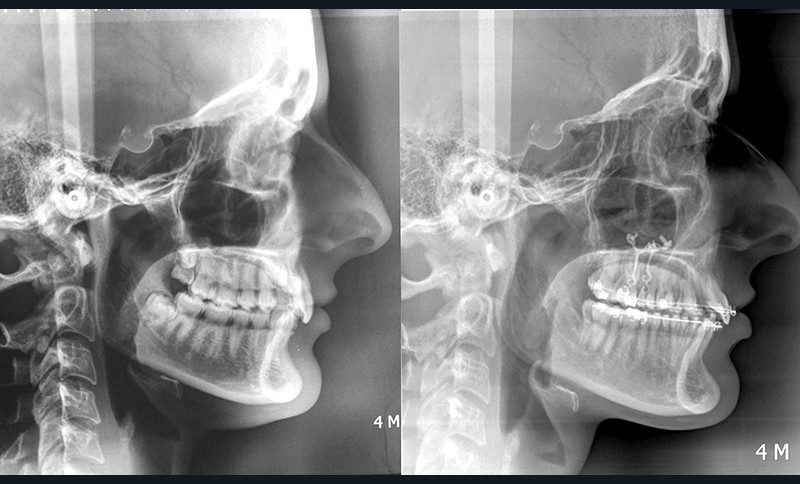

Aline se présente à la consultation pour une demande esthétique concernant ses deux canines lactéales qu’elle trouve trop petites et trop blanches (fig. 1a). Elle présente une classe II squelettique légère sur un schéma méso-divergent. D’un point de vue dentaire, une supraclusion est associée à une classe II d’Angle complète à gauche et de 4 mm à droite. Les canines maxillaires sont incluses (une vestibulaire et une palatine), avec persistance de leurs dents lactéales sur l’arcade (fig. 1b-h).

Traitement multi-attaches et contention

Un protocole orthodontico-chirurgical avec avancée mandibulaire est envisagé pour assurer un bon soutien labial, mais cette option est refusée par la patiente qui craint un visage trop carré. Concernant l’inclusion des canines maxillaires définitives, plusieurs thérapeutiques sont envisageables : 53, 63, 13, 23, ou 53, 63, 14, 24 peuvent être extraites, avec pour conséquence une classe II thérapeutique au niveau des molaires en fin de traitement. Cependant, la patiente souhaite mettre en place ses canines incluses pour conserver tout son capital dentaire et rétablir un idéal fonctionnel et esthétique au niveau des dents antérieures (fig. 2).

Dans un premier temps, des attaches bidimensionnelles (20/25 antérieures et 22/28 postérieures en Roth) sont collées aux deux arcades. L’alignement-nivellement est initié par des 0.014 Niti. Des plaques d’ancrages osseuses…